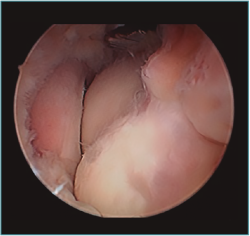

Cirugía artroscópica

La artroplastia osteocapsular artroscópica persigue los mismos objetivos que la cirugía abierta, con una serie de ventajas como son la menor incisión, la menor agresión para las partes blandas, la disminución del sangrado intraoperatorio y la mayor precisión en el fresado y recontorneado óseo, al contar con la magnificación proporcionada por la óptica, así como el mejor control del dolor del paciente en el postoperatorio y el comienzo precoz de la rehabilitación. Sin embargo, es un procedimiento demandante técnicamente que exige tener una amplia experiencia previa con procedimientos más simples. Los factores que aumentan la complejidad del procedimiento con respecto a otro tipo de artroscopias del codo son, dejando aparte los relacionados con la causa que desencadenó la rigidez, que ya fueron mencionados: el volumen articular reducido, la escasa distensibilidad de la cápsula engrosada y la presencia de cicatrices intraarticulares e hipertrofia sinovial, que dificultan de manera importante la visualización y el trabajo articular que tenemos que hacer. Esto, sumado a la restricción de 2 horas de isquemia como máximo de las que disponemos, puede poner en jaque a cirujanos inexpertos que tengan que terminar el procedimiento sin haber conseguido concluir los objetivos del tratamiento (Figura 7).

Figura 7. Sinovitis exuberante que no deja ver la articulación radiocapitelar desde el portal anteromedial proximal, en una artritis postraumática con volumen articular reducido.